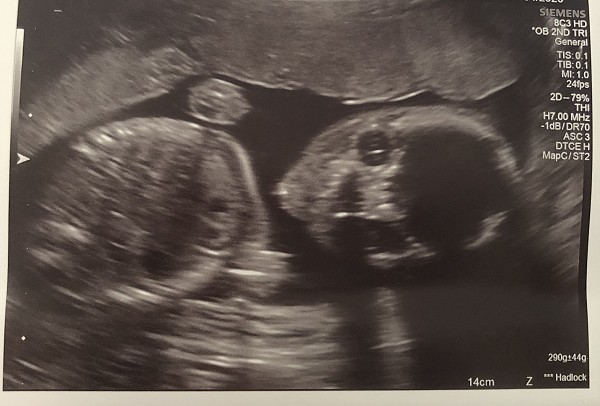

Elsewhere people have been gardening, and we have had another Newfield baby scan - see below!

Hi all - finally hit the half way mark - 20 weeks. Here’s my latest scan picture - the strangest I’ve seen as he or she was looking directly at the camera (taking selfies already!!) baby is fine, growing well and everything seems to be in the right place :). Looking forward to getting back to work and seeing all the staff and children. Take care

Shannon and baby